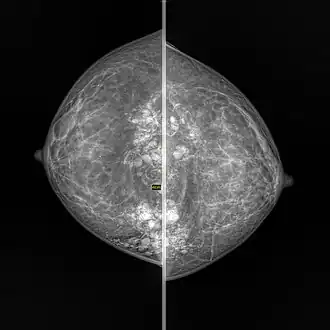

Silicone granuloma

Silicone granulomas are a skin condition that occur as a reaction to liquid silicones, and are characterized by the formation of nodules.[1]: 46

Formation of a granuloma is a common tissue response to a range of foreign bodies. Silicone can be directly injected into tissue as part of a cosmetic procedure or it can leak from silicone implants. The formation and consequences of silicon-induced granulomas is not well described or understood. The extent of damage that they cause is controversial.[2]

- Breast: Granulomatous mastitis[9][10]